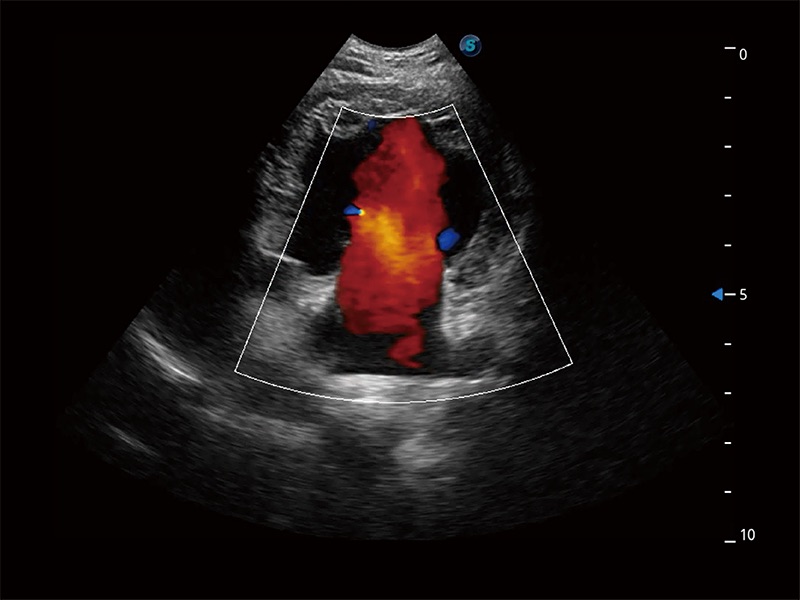

在传统二维血流成像的基础上,呈现血流的立体感,具有动感的生命力之美。即便是微小的血管也能轻松应对,提高了血流的视觉敏感性。